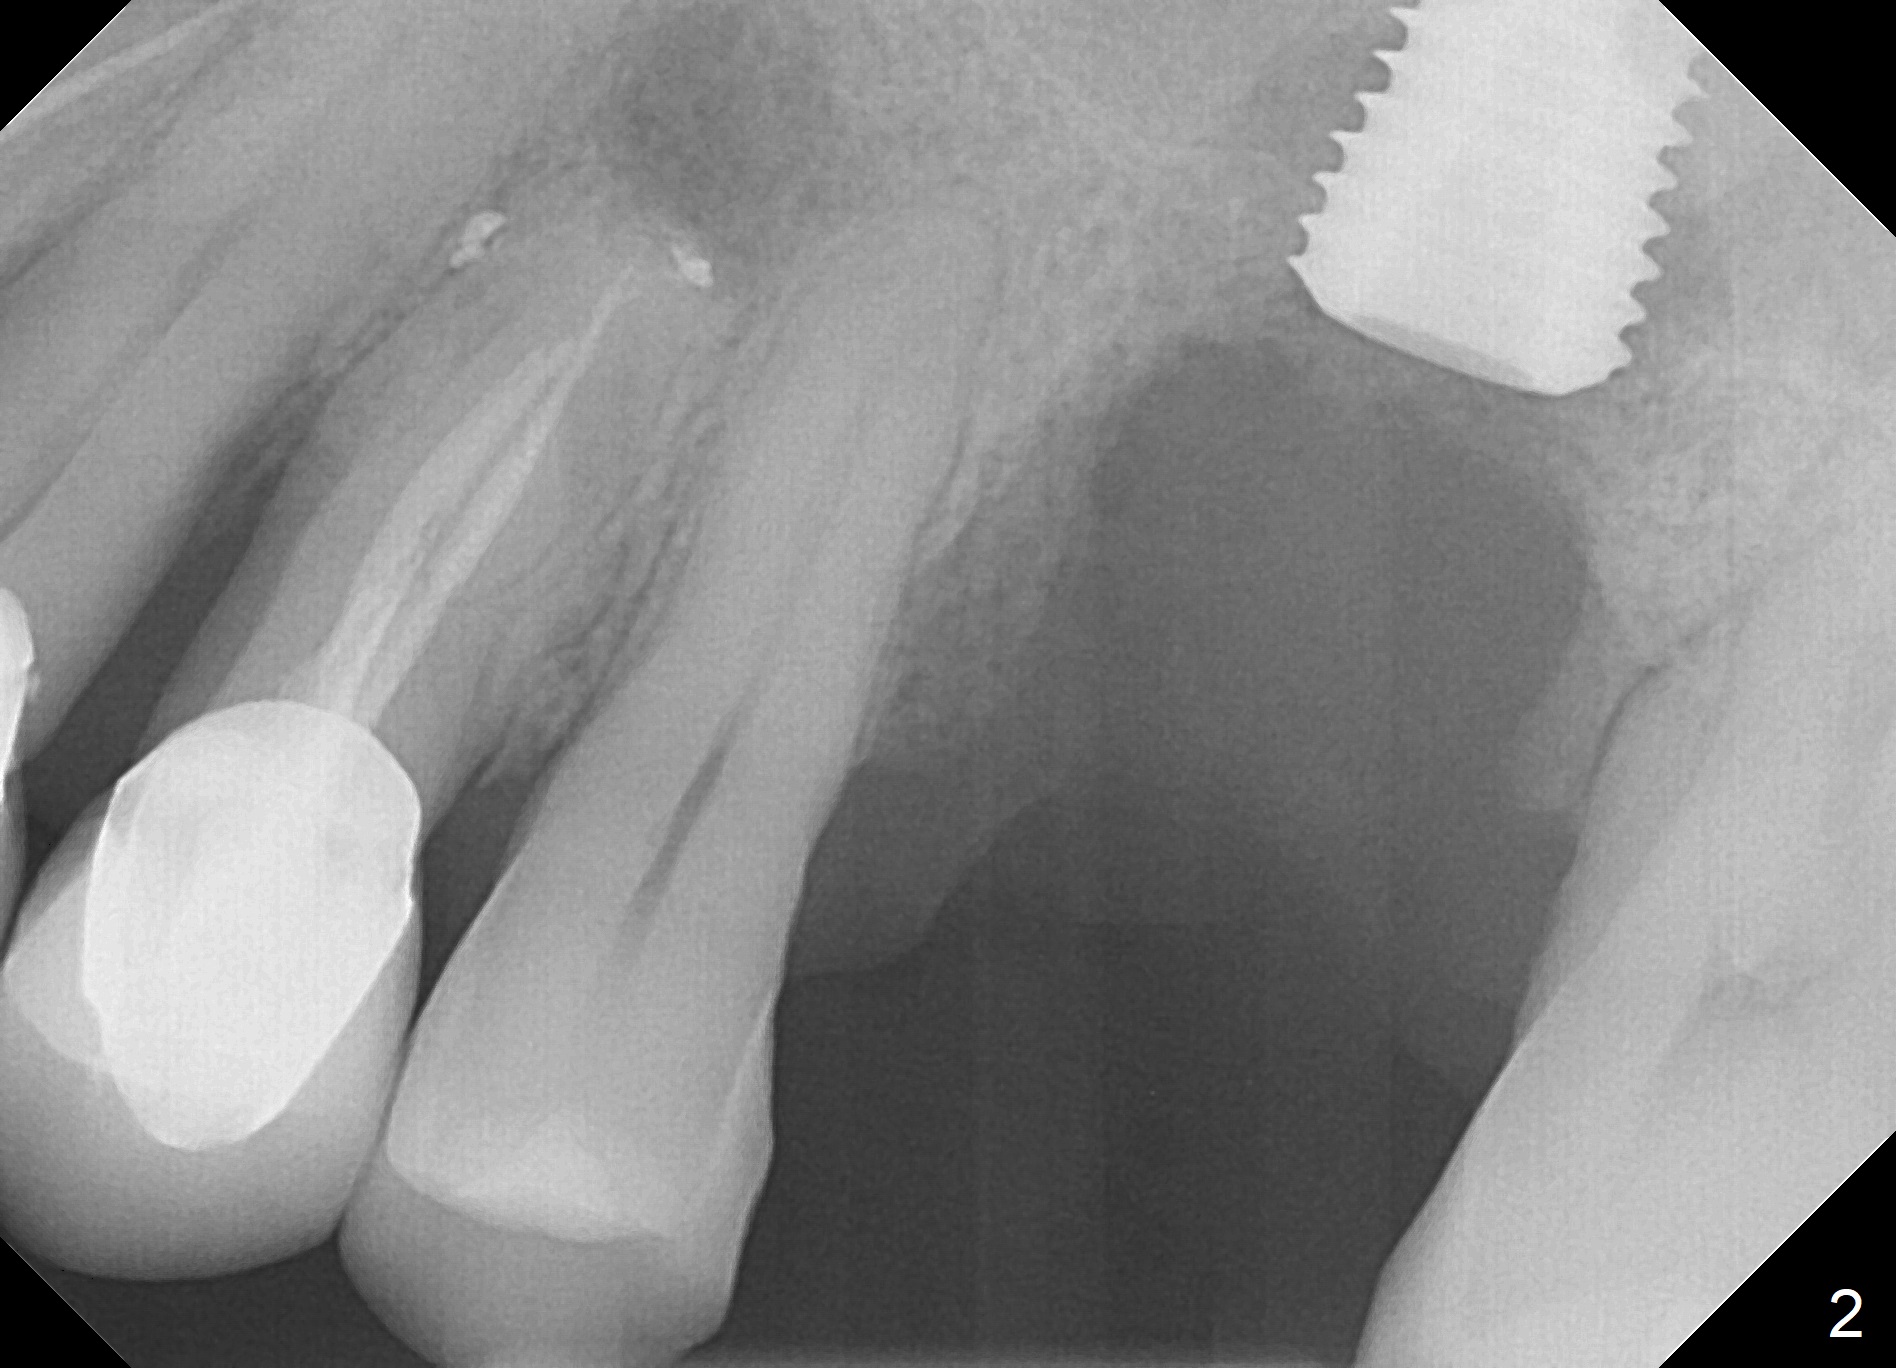

When the tooth #14 is extracted, the buccal plate is lost, while the apex of the palatal socket is perforated. The palatal slope of the septum appears to be a suitable site for osteotomy, but the depth seems to be 2 mm. After sequential osteotomy until 5.3 mm with drills, a 5.9 mm SM tap obtains stability (Fig.2). A 5.9x8 mmm implant is placed with barely sufficient stability after 1 piece of PRF membrane and VeraGraft (Fig.2-4). The implant rotates and dislodges when an abutment is being placed. Neither do 6-8x17 mm Tatum taps achieve primary stability. Socket preservation is performed, followed by periodontal dressing (Fig.5). Primary stability might have been obtained if a smaller IBS implant with fins were placed in the palatal socket. The periodontal dressing has dislodged 1 week postop; the socket appears healing (Fig.6,7). Bone graft seems to be minimal or bone density of the graft is low (Fig.8). The socket heals with a wide ridge 2 months post socket preservation, but the tooth #15 seems to be buccal (Fig.9) and mesial (Fig.10) shift. After use of Magic Split and Expanders (until 3.8 mm for 13 mm), try 5 mm dummy implant (Fig.11). If 6 mm one fails to achieve stability substantially, switch to 7 mm Tatum tapered tap provided there is enough mesiodistal space (use 8 mm implant positioner to gauze the space beforehand (preop)). Consider using Vanilla (not Vera) Graft to fill in the gap between implant and osteotomy. When primary stability is obtained, place a nonfunctional provisional to prevent further shifting (Fig.11 white outline). After osteointegration, use the provisional (reline and separator) to distalize the tooth #15.